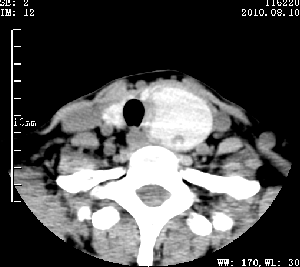

标题: CT28317:病人近几天无意间发现颈部肿块。 [打印本页]

标题: CT28317:病人近几天无意间发现颈部肿块。

甲状腺左叶局限性结节性甲状腺肿可能。建议增强扫描。

病变边界清楚,周围间隙清晰,甲状腺左叶(甲状旁腺?)肿大,右叶甲状腺腺瘤。

病变边界清楚,周围间隙清晰,左叶甲状腺肿大,右叶甲状腺小腺瘤。